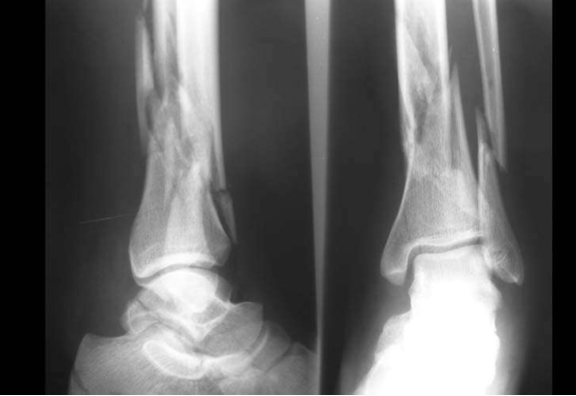

Define a stress fracture?

How are they detected?

Repeated low force injury to a normal bone

Use bone scan to see where tissue is active